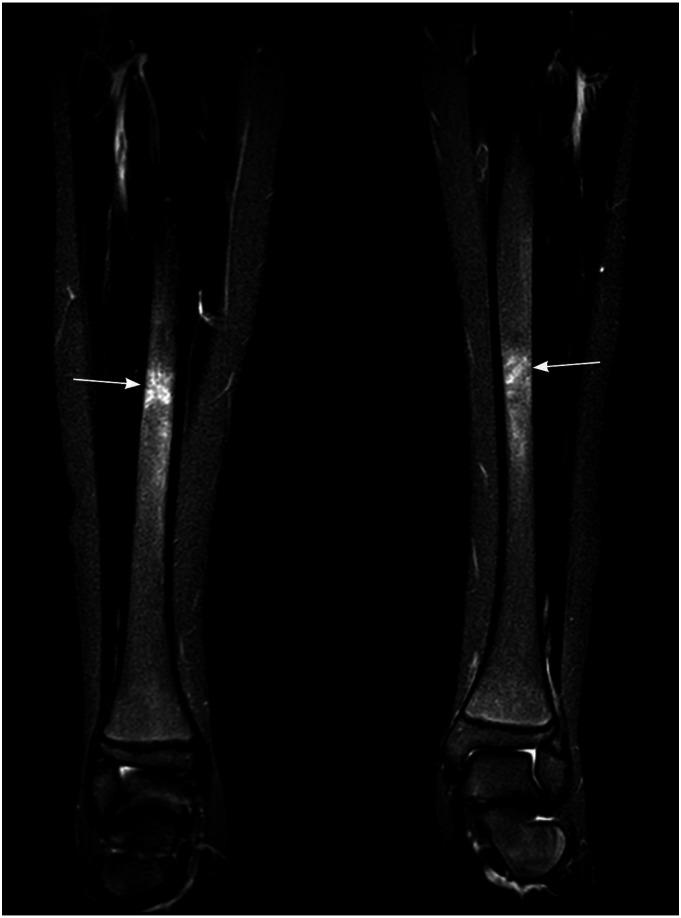

Whole-body magnetic resonance imaging studies of all children with documented CNO, performed in a single tertiary center, were retrospectively reviewed. WBMRI included coronal T1 and short-tau inversion recovery (STIR), whole spine sagittal STIR, and ankle/foot sagittal STIR images. High signal intensity lesions on STIR images corresponding to bone marrow edema were recorded. The SPSS v.20 statistical package was used for descriptive statistics.

Twenty children were included (mean age: 12, range: 6-16 years) with 1-31 lesions (mean: 11.8) on WBMRI. Two children had unifocal disease localized at the clavicle, three paucifocal (1-4 lesions), and 15 multifocal bone involvement. All but two children presented with ankle pain and exhibited lesions at the bones of the ankle joint (90%) followed by the knee (50%) and pelvis (10%). The tibia was the most frequently affected bone (70%) followed by calcaneus (60%), fibula (50%), femur (45%), talus, and metatarsals (45%). No lesions in the cervical, thoracic, lumbar spine, and mandible were documented. Only small sacral lesions were seen in 25% of patients with the extensive peripheral disease. Bilateral metaphyseal and epiphyseal involvement with transphyseal extension were common, but the periosteal reaction and well-defined lesion margins were rare.

纳入20名儿童(平均年龄:12岁,范围:6 - 16岁),WBMRI上有1 - 31个病变(平均:11.8个)。2名儿童为单病灶疾病,局限于锁骨;3名儿童为少病灶(1 - 4个病变);15名儿童为多病灶骨受累。除2名儿童外,所有儿童均有踝关节疼痛,且踝关节骨骼出现病变(90%),其次是膝关节(50%)和骨盆(10%)。胫骨是最常受累的骨骼(70%),其次是跟骨(60%)、腓骨(50%)、股骨(45%)、距骨和跖骨(45%)。未记录到颈椎、胸椎、腰椎和下颌骨有病变。仅25%有广泛外周疾病的患者可见小的骶骨病变。双侧干骺端和骨骺受累并伴有骨骺延伸很常见,但骨膜反应和边界清晰的病变边缘很少见。